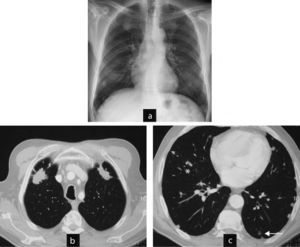

Case 4 (Fig. 3)This patient was a 66-year-old male, diagnosed with RA for 9 years, RF positive and an ex-smoker. A year ago he was diagnosed with interstitial lung disease with respiratory symptoms, moderate dyspnea and mild restrictive respiratory failure. A control CT detected, one year later, rounded subpleural pulmonary nodules. The patient required follow-up.

Cases 4 and 5. Different clinical settings: surgical biopsy or control image. (a) Case 5: chest CT: non-specific nodules in a patient without a diagnosis of joint disease and respiratory symptoms. The patient was diagnosed with necrotizing granulomas requiring surgical biopsy. The patient developed rheumatoid arthritis a year later. (b) Case 4: CT scan of the chest: nodules with typical radiological aspect of rheumatoid nodules, rounded, subpleural and multiple in a patient with rheumatoid arthritis associated with interstitial lung disease. Control image.

This patient was a 47-year-old woman with no known joint disease. A chest radiograph due to coughing and expectoration found multiple pulmonary nodules. Computed tomography revealed that the nodules were millimetric, rounded, predominantly peripheral, subpleural, located in the upper lobes. A surgical biopsy of the nodules was made with the diagnosis of necrotizing granulomas. A year after symptoms, she presented joint swelling and was diagnosed with RA. In subsequent tests the nodules were stable without associated respiratory symptoms.